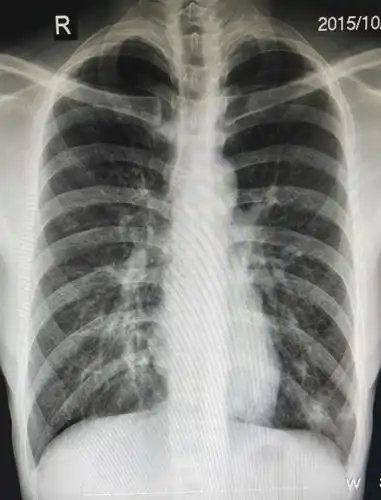

肺炎患者x线片